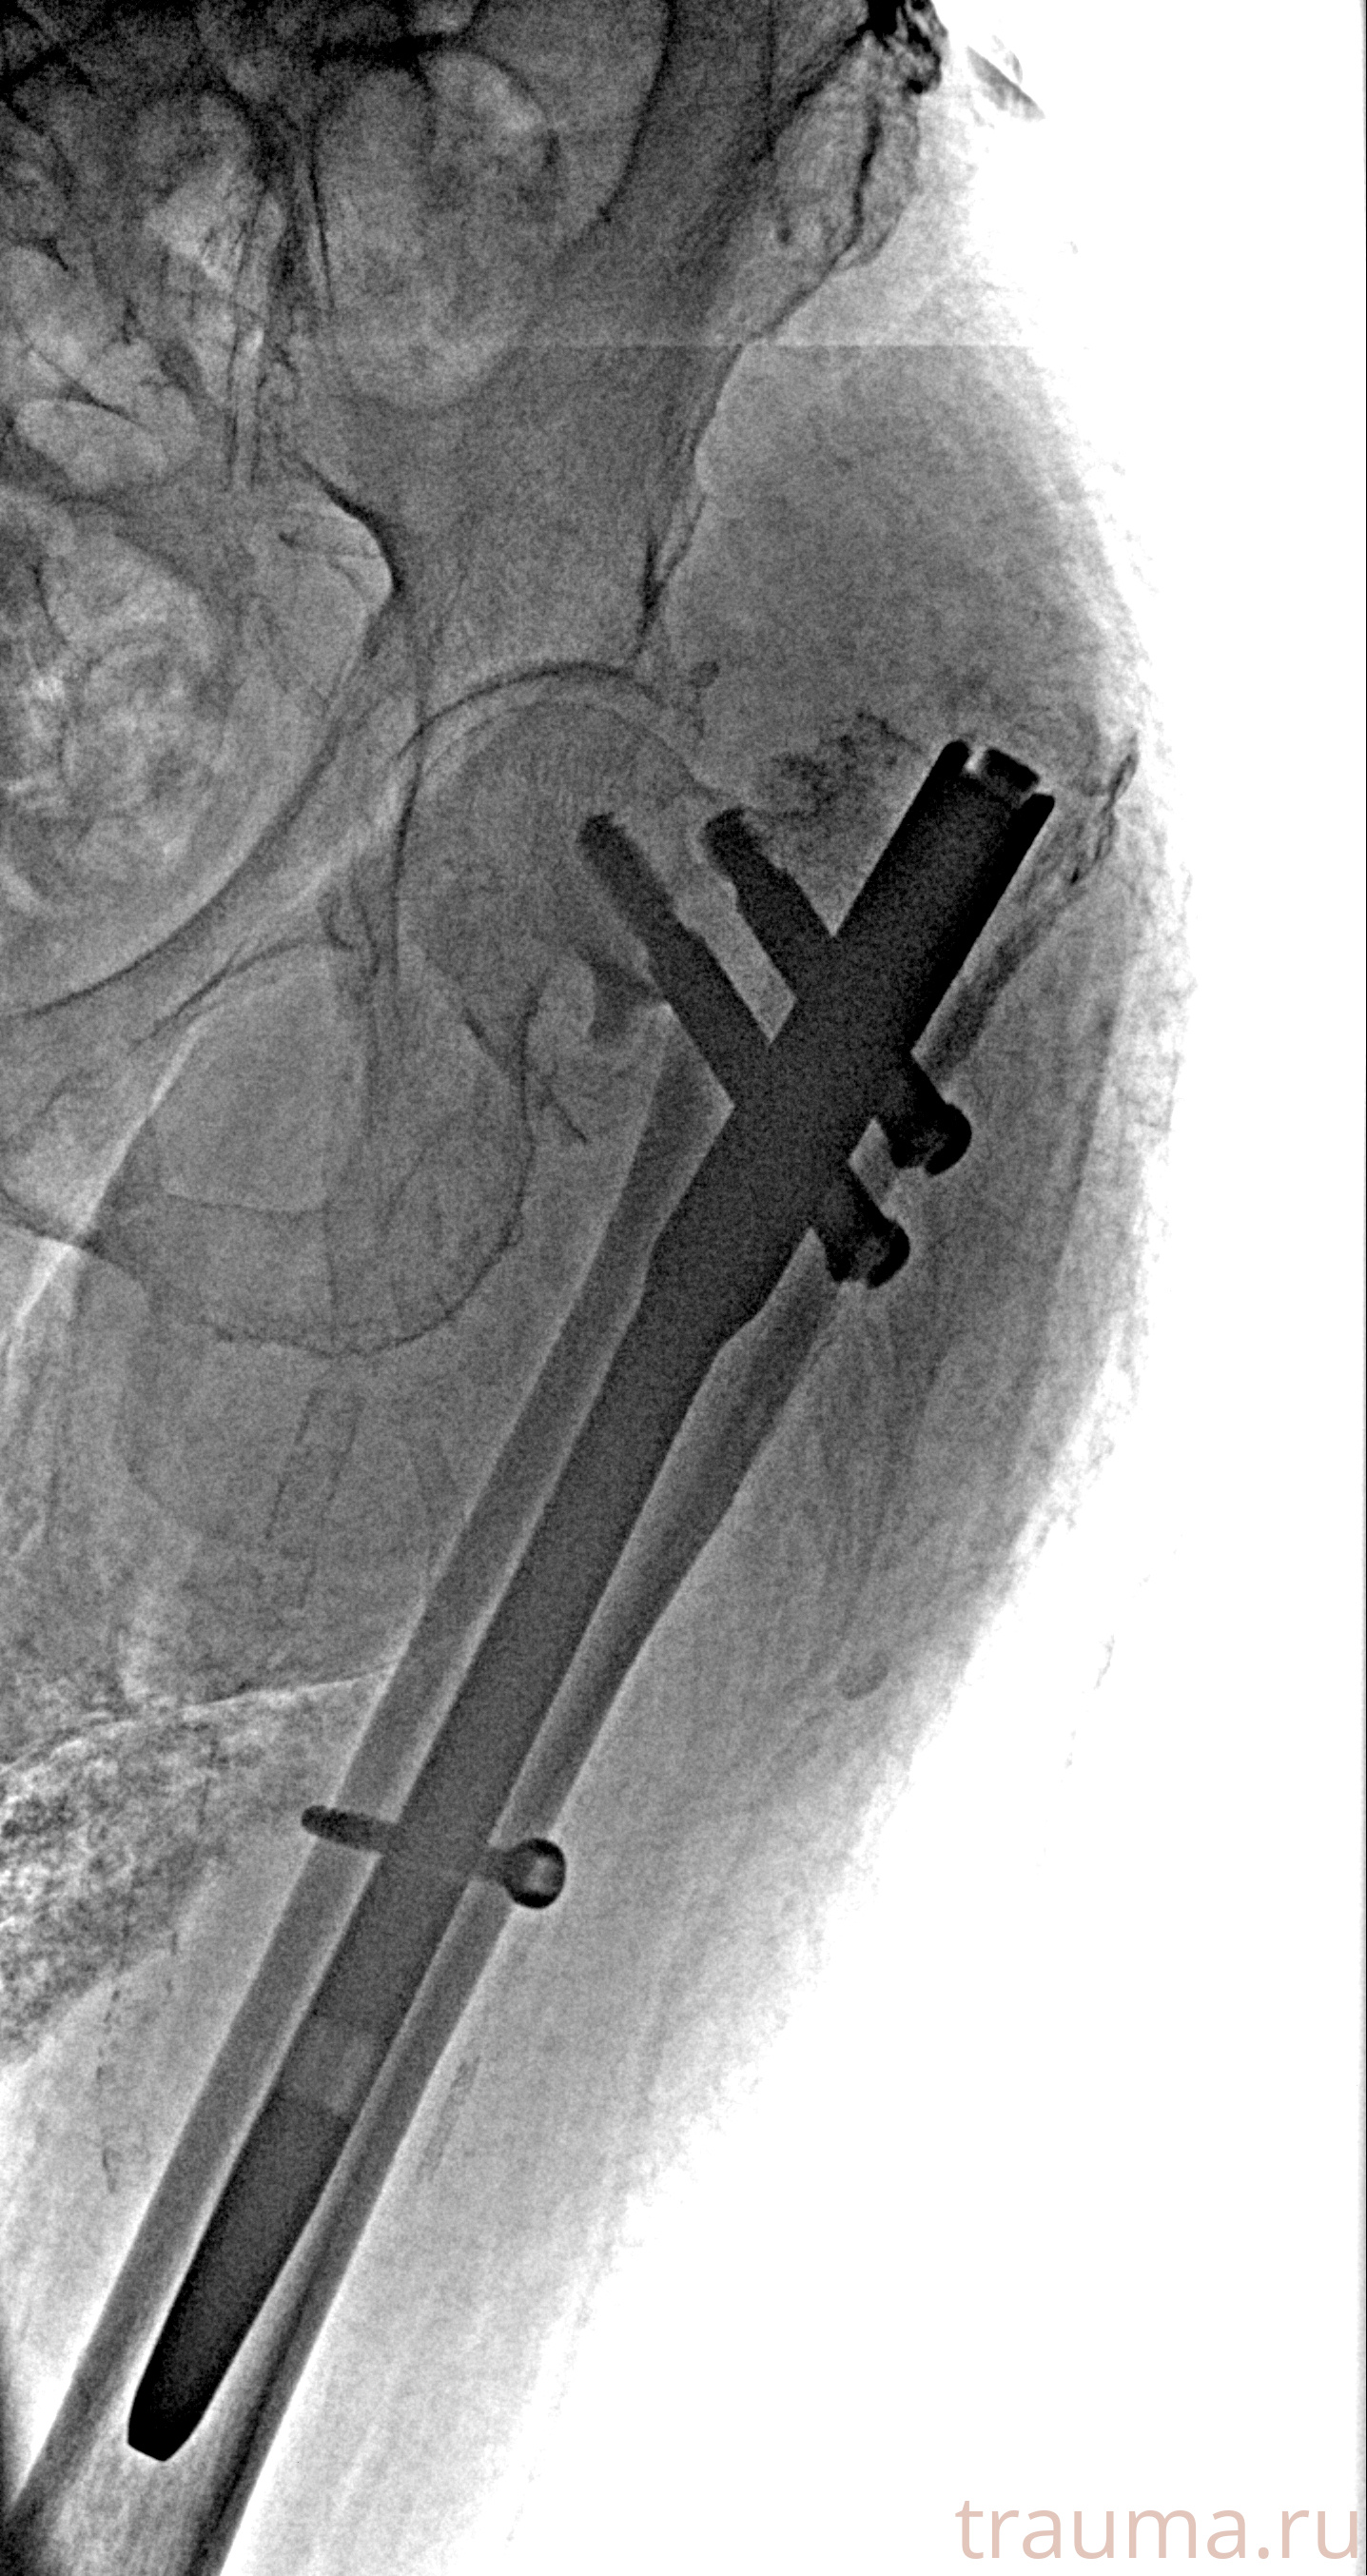

Рентгенограммы

Рентген на дому: по вашему адресу приезжает врач-рентгенолог, травматолог-ортопед с мобильным рентгеновским аппаратом, проводит диагностику травмы или заболевания, делает необходимые рентгенограммы, дает рекомендации по дальнейшему лечению. Получить качественные снимки в домашних условиях возможно благодаря уникальной методике, разработанной МосРентген Центром для института  Склифосовского

при переломе шейки бедра и пневмонии от компании МосРентген Центр - партнера Института имени Склифосовского